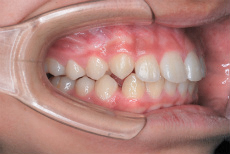

上あご前歯が前方に傾斜しており、しかも相対的に下あごが後退している上顎前突(出っ歯)の状態です。

まずこのような取り外しのできる装置を上あごに夜間のみ8か月間装着していただきました。

この装置を装着した目的は上あごの歯列幅拡大に加えまして、上あご前歯を後ろに引っ込めるためです。

次に上あご歯列幅拡大後に機能的矯正装置(下あごの前方への成長を誘導する装置)を3年間使用しました。この装置の装着期間ですが、乳歯がすべて永久歯に交換するまでの期間になります。